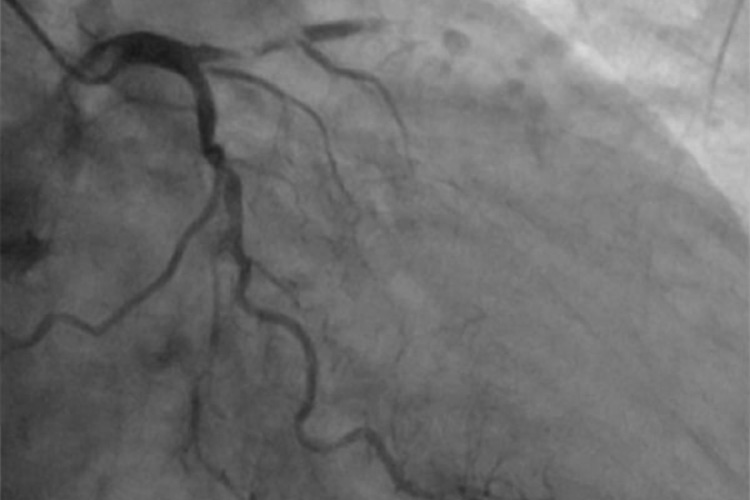

①カテーテル治療(PCI)

検査と同様に手首や肘、足の付け根の動脈からカテーテルを冠動脈まで持っていき、カテーテルに装着したバルーンで広げ、更にステントを拡げることで血流を維持します。しかし、金属製ステントの周りに血栓が出来やすくなるのが欠点で、血栓を予防するための抗血小板薬は欠かせません。

心臓カテーテル治療のイメージ

心筋梗塞ではいかに早く冠動脈の血流を再開させるかが大切になります。その点、心臓カテーテル治療(PCI)は冠動脈へのアクセスが早いため第1選択になのですが、PCIでは治療できない、あるいはリスクが高すぎる場合があります。